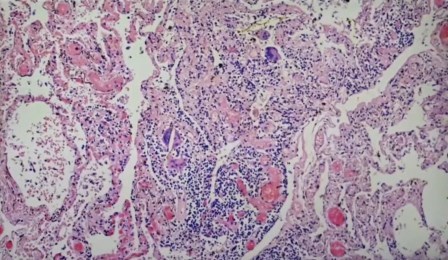

Vasos sanguíneos, endotelitis

El endotelio es la capa que recubre los vasos, son tan pequeños que normalmente no se ven.

Linfocitos en endotelio, endotelitis

Foco de infección, inflamación no sólo de los vasos sanguíneos, sino múltiple.

Atelectasis, pulmón colapsado

Aglomeración de linfocitos alrededor de un vaso

«Esto no es autolisis y lo vemos una y otra vez, con desprendimiento del endotelio de los vasos, entotelitis», exclama el científico. Terrible.

«Antes no lo había visto, y yo he visto mas de 40 mil autopsias y 500 mil biopsias, estas células que se han desprendido no es autolisis, porque hay también eritrocitos, que son las células largas, y no pueden estar allí después de la autolisis y lo vemos una y otra vez. Hay desprendimiento de células endotélicas», detalla.